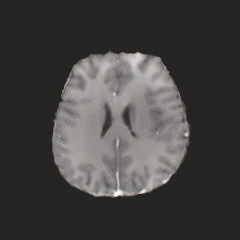

Multi-modal medical image completion has been extensively applied to alleviate the missing modality issue in a wealth of multi-modal diagnostic tasks. However, for most existing synthesis methods, their inferences of missing modalities can collapse into a deterministic mapping from the available ones, ignoring the uncertainties inherent in the cross-modal relationships. Here, we propose the Unified Multi-Modal Conditional Score-based Generative Model (UMM-CSGM) to take advantage of Score-based Generative Model (SGM) in modeling and stochastically sampling a target probability distribution, and further extend SGM to cross-modal conditional synthesis for various missing-modality configurations in a unified framework. Specifically, UMM-CSGM employs a novel multi-in multi-out Conditional Score Network (mm-CSN) to learn a comprehensive set of cross-modal conditional distributions via conditional diffusion and reverse generation in the complete modality space. In this way, the generation process can be accurately conditioned by all available information, and can fit all possible configurations of missing modalities in a single network. Experiments on BraTS19 dataset show that the UMM-CSGM can more reliably synthesize the heterogeneous enhancement and irregular area in tumor-induced lesions for any missing modalities.